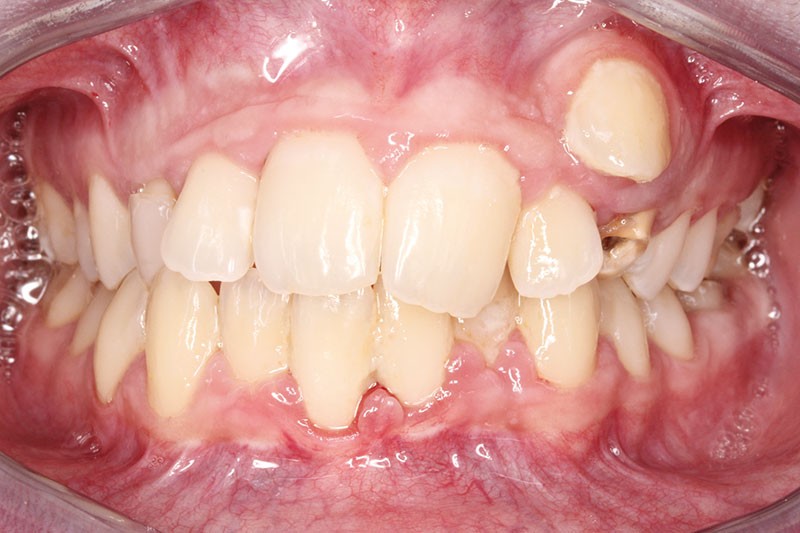

De face, Younesse présente un sourire gingivo-dentaire dissymétrique par contraction labiale unilatérale et un milieu inter-incisif dévié à droite de 2 mm par rapport au plan sagittal médian (fig. 2).